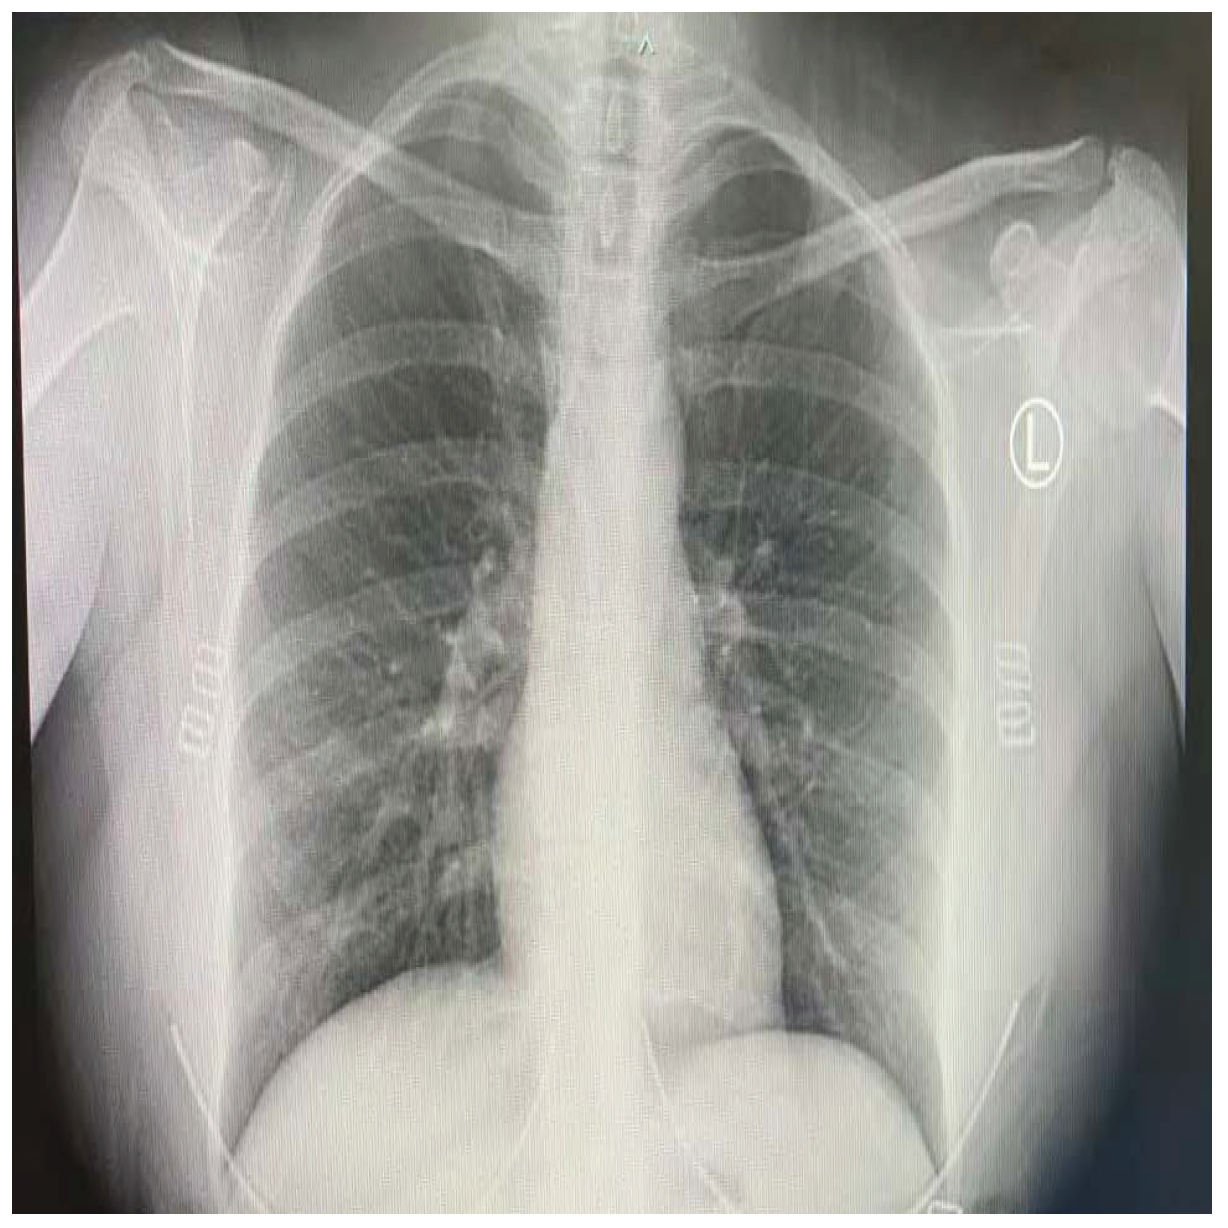

COVID-19 patients who have clinical symptoms are more likely to show abnormal CXR [9]. The main findings of recent studies suggest that these lung images display patchy or diffuse reticular–nodular opacities and consolidation, with basal, peripheral, and bilateral predominance [10]. For example, Figure 1 shows the CXR of a mild case of lung tissue involvement with right infrahilar reticular–nodular opacity. Moreover, Figure 2 shows the CXR of a moderate to severe case of lung tissue involvement. This CXR shows right lower zone lung consolidation and diffuse bilateral airspace reticular–nodular opacities, which are more prominent on peripheral parts of lower zones. Similarly, Figure 3 shows the CXR of a severe case of lung tissue involvement. This is caused by diffuse bilateral airspace reticular–nodular opacities that are more prominent on peripheral parts of the lower zones, and ground glass opacity in both lungs predominant in mid-zones and lower zones. On the other hand, Figure 4 shows an unremarkable CXR with clear lungs and acute costophrenic angles (i.e., normal).

Figure 2.

CXR of COVID-19 subject showing moderate to severe lung tissue involvement.